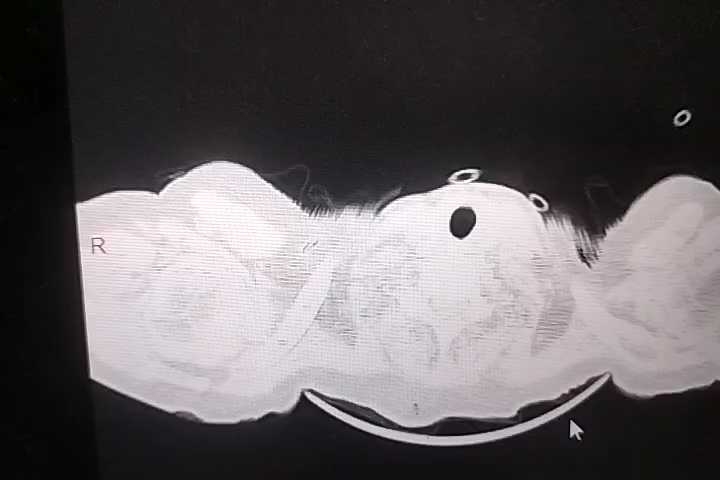

胸部+全腹部CT结果回报:双肺支气管炎,通气不良,双肺底多发索条,考虑1、膨胀不良2、慢性炎症,左肺下叶钙化灶,主动脉钙化,食管裂孔疝,纵隔多发淋巴结,肝门区钙化灶,胆囊密度低密度增高,考虑胆汁淤积,右肾囊肿?建议强化,双肾盂、输尿管扩张,膀胱过度充盈,考虑尿潴留,结合临床,直肠积粪密切观察病情变化。